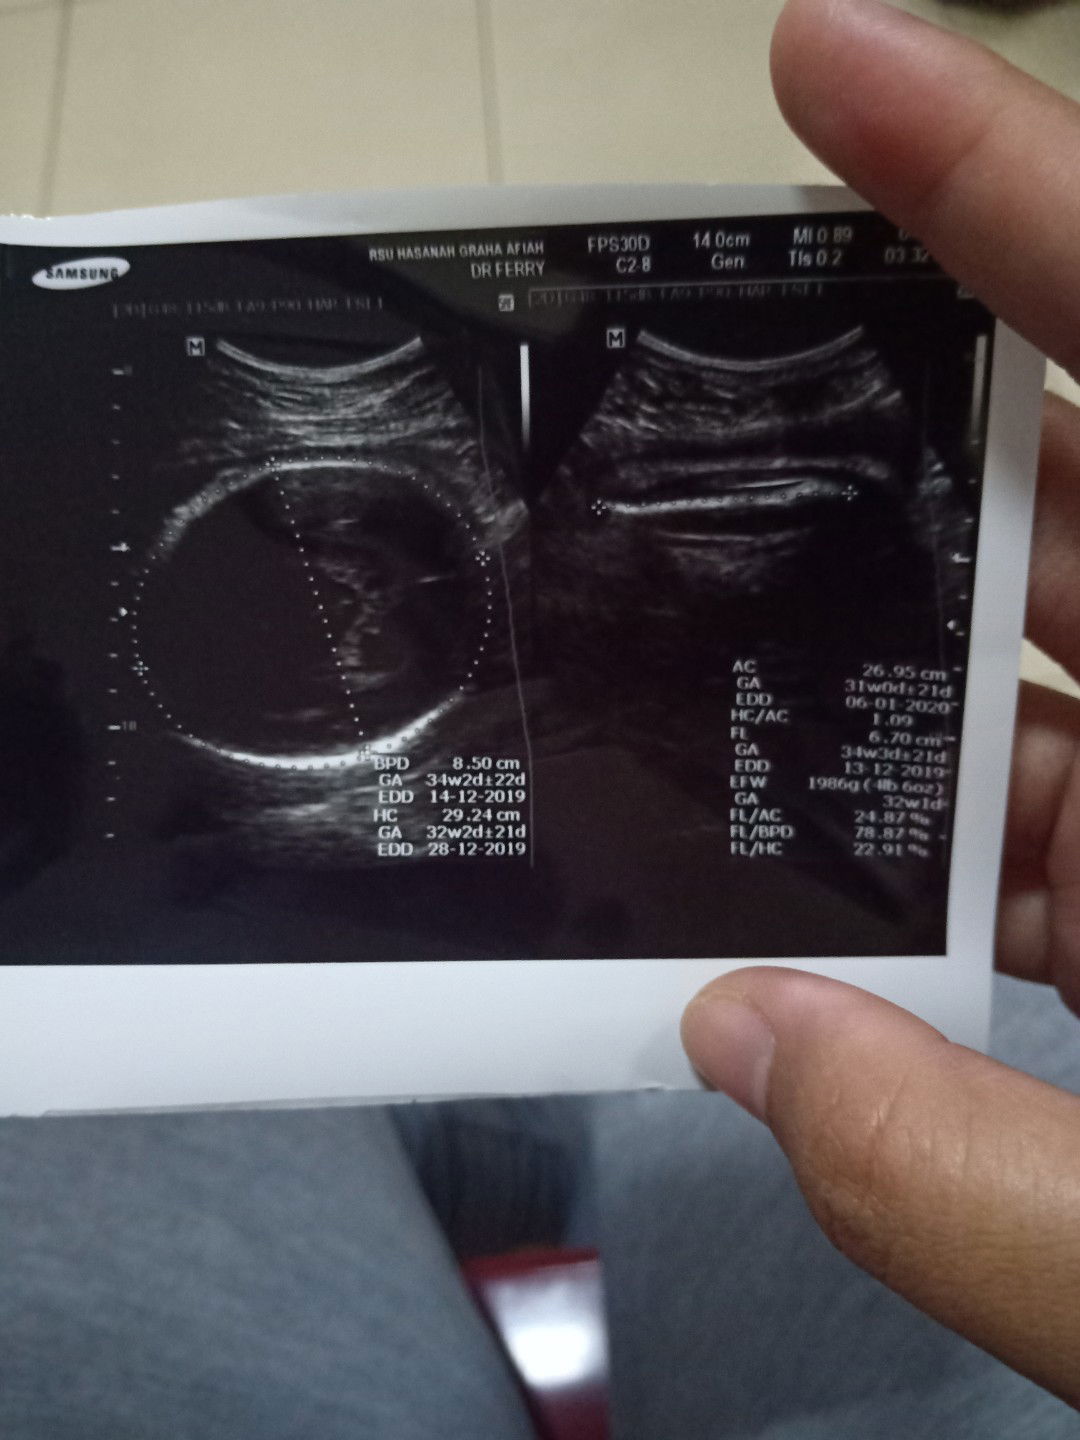

Yang bener yang mana yaa

buun, usia kemahilan ku kalo di usg 29 week, tapi kalo periksa kebidan 31 week.. yang lebih akurat yang mana yaa bun?? dan Hplnya di usg bulan desember, kalo kata bidan november.. jadi bingung nih buunn..